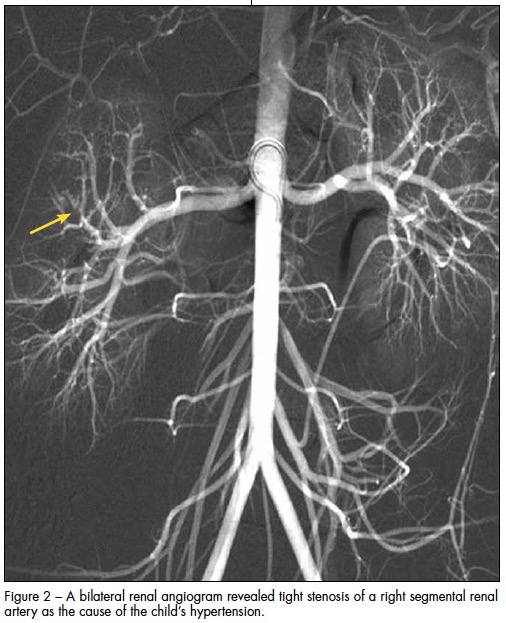

Renal Doppler ultrasonogram was normal. MRI scan of the brain revealed no intracranial pathology. However, while the patient was sedated for the MRI, automated blood pressures were 180/106 mm Hg and 177/110 mm Hg. This prompted an extensive evaluation for secondary hypertension. Results showed a plasma renin level of 4785 ng/dL and a serum aldosterone level of 89 ng/dL. A bilateral renal arteriogram revealed tight stenosis of a right segmental renal artery (Figure 2).